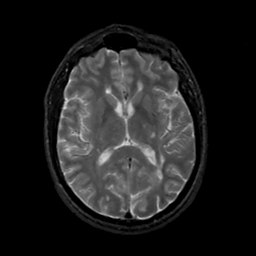

MR Study #12, May 12, 1991 -- Slice #27